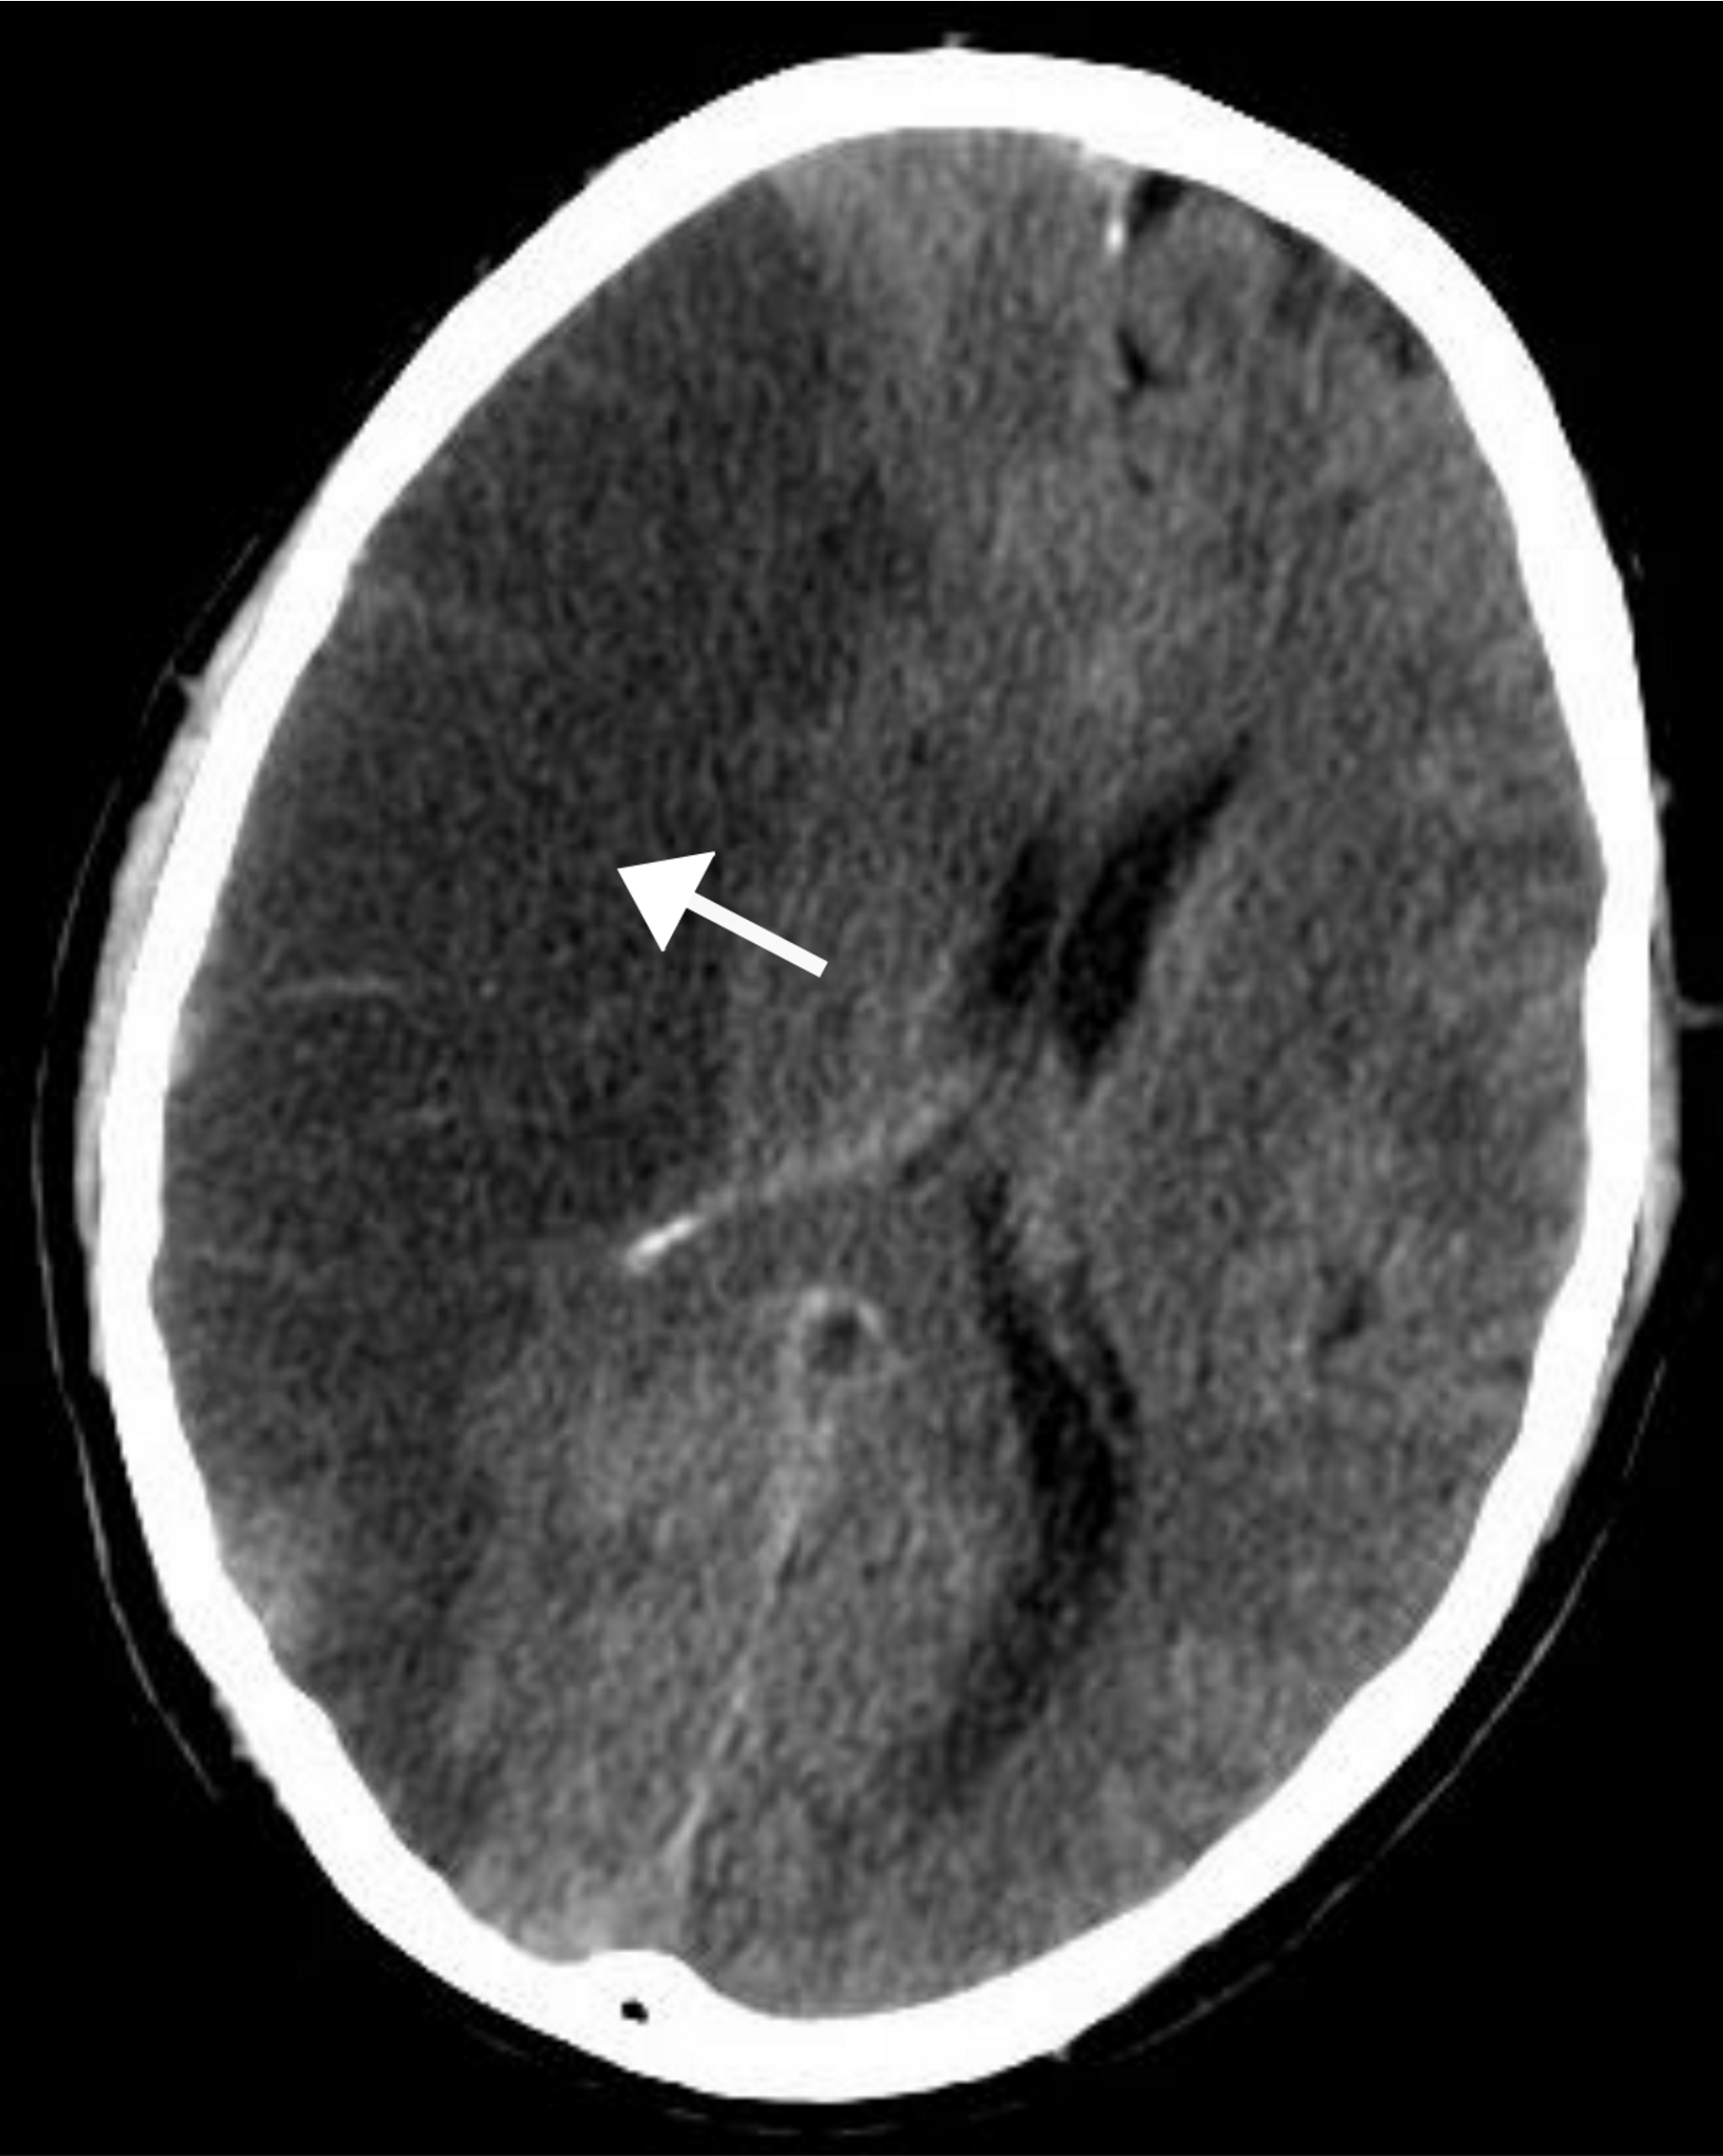

Traumatic vascular injury (epidural, subdural, subarachnoid)

(pathogenesis + signs + CT + treatment)

Pathogenesis:

Epidural haematoma: tearing of middle meningeal arterty following fracture of temporal bone, where arterial pressure forms rapidly expanding haematoma

Subdural haematoma: rupture of bridging veins (usually in elderly patients with cerebral atrophy)

Subarachnoid haematoma: injury to BV (e.g. burst aneurysm) in subarachnoid space

Diagnosis - CT:

Epidural haemorrhage: hyperdense biconvex mass stopping at suture line, midline hift and ventricular compression

Subdural haemorrhage: hyperdense/ isodense sick shape over cerebal convexity, midline shift and ventricular compression

Subarachnoid haemorrhage: star-shapped appearance around circle of willis; severe ‘thunderclap’ headache